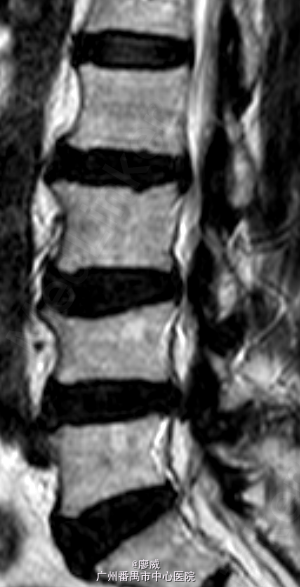

主诉:腰痛2年余,左小腿外侧麻痛半月。 病史:男性患者,52岁。患者2年前在做体力活时出现腰部剧烈疼痛,当时腰部活动受限,在外院门诊诊断为腰肌劳损,给予对症治疗,效果较好。2年来活动后腰部均出现疼痛,反复出现。最近半月以来,患者腰部疼痛时间延长,加重,并伴左小腿外侧麻木,放射痛至足踝处。患者一般情况尚可。

体查:左小腿外侧区域感觉减退;左侧直腿抬高试验50°(+),其余未见明显异常。 辅助检查:三大常规、血生化、肝肾功能均未见明显异常。患者腰椎动力位片正常,其余重要腰椎影像学如下。

目前诊断:腰椎间盘突出症。 处理:入院后完善相关检查,术前给予对症治疗,科里术前讨论决定:拟行手术:椎间孔镜下L4/5椎间盘摘除+椎间孔扩大成形+射频消融术。

讨论:该患者在影像学上看有多个节段的腰椎间盘突出,但最严重的是L4/5,结合患者临床症状及体查,主要也是L4/5。这虽然术后的情况说不定,也许完全缓解,也许还残留其他节段存在的问题。